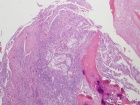

72 year old man with R hip pain since fall in 12/05

Zoom image: Cell stain Cell stain.